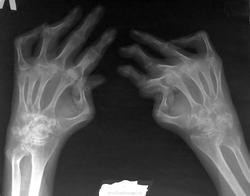

Вот это даа.... не встречалось пока ничего подобного. Сколько же лет человек страдает РА?

Кстати, на данной рентгенограмме хорошо видна деформация "шея лебедя" (ІІ-ІІІ палец правой руки)

Вот поленился указать, что это начало IV стадии, теперь оправдываться…. Но тут, пока я слушал Прекрасную Музыку, внезапно пришла помощь, откуда не ждали: один Андрей отбил атаку другого)). А Петровича дружно реабилитировали.

Quarta, ребята, это по-латински – четвёртая. IV стадия. Последняя и безнадёжно необратимая для многих болезней.

При всем уважении к Петровичу, с IV стадией не соглашусь. 4-я - это анкилоз, а тут 3-я - девиации и подвывизи/вывихи.

Сомнительная 3-я, но ни как не 4-я...

Чтоб не сомневались, цитата из известного пособия Михайлова, Володиной, Ларюковой "Диф. диагностики КСС" :

Американская ревматологическая ассоциация предлагает выделять 4 стадии процесса по степени рентгенологических изменений.

Iстадия — ранняя. При рентгенологическом исследовании выявляется сначала регионарный остеопороз в околосуставных отделах, т. е. в участках богатых губчатым веществом. При не адекватном или не своевременном лечении развивается диффузный остеопороз. Остеопороз носит функциональный характер. За счет эксудации в полость сустава развивается болезненность и как следствие — ограничение движений.

IIстадия — умеренная. На рентгенограммах рядом с суставной поверхностью субкортикально определяются множественные мелкие, до 2—3 мм в диаметре кистоподобные просветления с четкими ровными контурами и ободком склероза вокруг. Может отмечаться разрушение кортикального слоя с образованием четкоочерченных ограниченных ободком склероза краевых узур. Суставные щели представляются суженными.

IIIстадия — тяжелая. Количество узур увеличивается, суставные щели представляются суженными, суставные поверхности становятся инконгруентными. В межфаланговых суставах развивается ульнарная девиация, т. е. латеральный подвывих и смещение.

IVстадия — последняя. К рентгенологическим симптомам IIIстадии присоединяются явления анкилоза. Анкилоз — сначала фиброзный, а затем костный. Развивается в пястно-запястном сочленении, распространяется проксимально и все 8 костей запястья могут представляться в виде единого костного блока.

Все правильно, но здесь же есть анкилозы в межзапястных суставах.

Вот поленился указать, что это начало IV стадии, теперь оправдываться…. Но тут, пока я слушал Прекрасную Музыку, внезапно пришла помощь, откуда не ждали: один Андрей отбил атаку другого)).